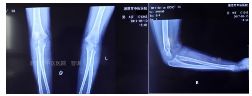

外院片如下:

杨氏四步复位法整复后拍片复查